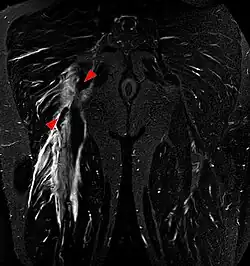

Tear of the hamstrings muscles at the ischial tuberosity seen on MRI (visible on a coronal STIR MRI sequence). The arrowheads indicate the tuber and the retracted tendon stump. Significant bleeding around and into the muscles.

Imaging the hamstring muscles is usually performed with an ultrasound and/or MRI.[9]  The biceps femoris is most commonly injured, followed by semitendinosus. Semimembranosus injury is rare. Imaging is useful in differentiating the grade of strain, especially if the muscle is completely torn.[10] In this setting, the level and degree of retraction can be determined, serving as a useful roadmap prior to any surgery. Those with a hamstring strain of greater than 60 mm (2.4 in) in length have a greater risk of recurrence.[11]